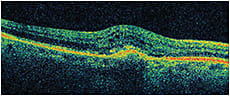

Visual acuity measured 20/100+1 OD and 20/25-2 OS. Fluorescein angiography revealed a subfoveal classic choroidal neovascular membrane with leakage OD. Figure 1 shows his OCT at baseline. He received three monthly bevacizumab injections OD with limited response in vision and on OCT, (Figures 2-3). He then received aflibercept OD. Despite missing a monthly appointment, the patient had noted improvement in vision at 2 months after injection, and the examination documented improvement in visual acuity and macular thickness on OCT (Figure 4).

Figure 4. OD, 2 months after aflibercept injection, VA 20/60+2, CMT 285.